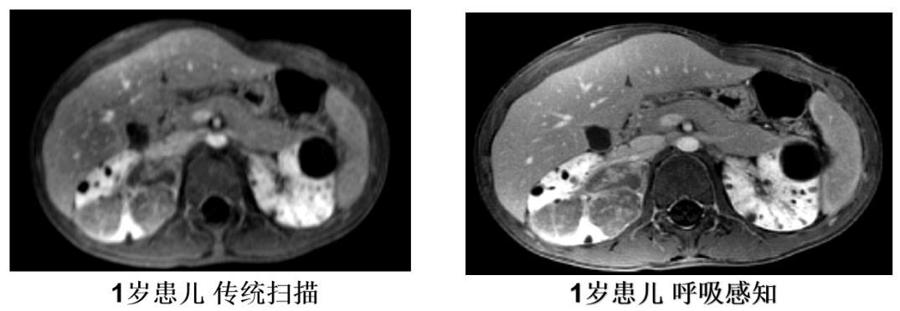

03自由呼吸成像平台

传统的磁共振成像对运动都非常的敏感,为了在体部获得有价值的诊断图像,体部磁共振成像要求患者屏气扫描。新设备配置了自由呼吸成像平台,结合呼吸感知功能,可以精确控制体部扫描的每次信号采集,采用运动不敏感的扫描方式,并进行运动校准得到精准的图像。这种创新性采集方式对于病人的任何运动都不敏感,保证极高运动脏器成像质量。